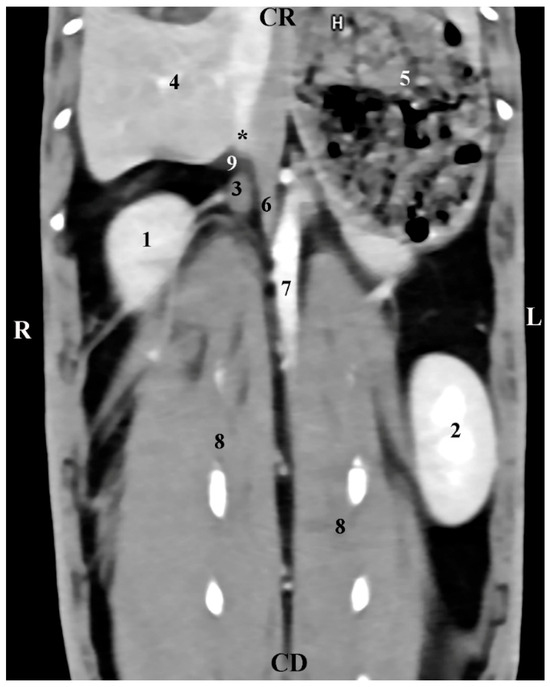

The transverse post-contrast CT anatomical investigation at the level of the 12th thoracic vertebra (Th12) gave complete information about the topographic location and shape of the right adrenal gland. The latter was a retroperitoneal soft tissue finding located in the intrathoracic part of the abdominal cavity. The gland was localized on the right of the median plane, in the dorsal abdominal quarter. It was detected dorsally and in close proximity to the contrast-enhancing v. cava caudalis, the aorta abdominalis, and the liver. The borders of the right adrenal were sharply delineated, which defined it as an ellipse-shaped structure. The soft tissue attenuation of the gl. adrenalis dextra was relatively lower than that of the right liver lobe (Figure 1).

Figure 1. Transverse CT post-contrast anatomical study of the rabbit abdomen at the level of Th12. L—left; R—right. (1) aorta abdominalis; (2) v. cava caudalis; (3) right adrenal gland; (4) lobus hepatis dexter; (5) caecum; (6) duodenum; (7) ileum; (8) corpus ventriculi; (9) fundus ventriculi.